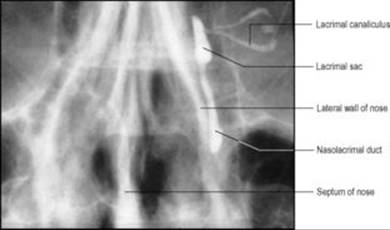

At the medial end of each lid margin is a low elevation, the lacrimal papilla, surmounted by a minute lacrimal punctum. This opens into a lacrimal canaliculus, a tiny canal which conveys excessive tears to the lacrimal sac (Fig. 6.52).

Magnified view of a left dacrocystogram (lacrimal canaliculogram).

The lacrimal sac lies in the lacrimal groove formed by the maxilla and lacrimal bone, crossed in front by the medial palpebral ligament, and some deeper fibres of orbicularis oculi are inserted into the walls of the sac (see p. 350). When the palpebral and lacrimal parts of orbicularis oculi contract, the lids are closed and the puncta turned inwards to dip into the lacus lacrimalis. Simultaneously the sac is drawn widely open, so that tears are sucked in through the canaliculi.

The nasolacrimal duct, 2cm long, slopes downwards, backwards and laterally, in conformity with the pear-shaped nasal cavity, to open high up in the anterior part of the inferior meatus 2cm behind the nostril. The mucous membrane is raised into several variable folds which act as valves to prevent air being blown up the duct into the lacrimal sac. The duct and sac are lined by ciliated columnar epithelium.